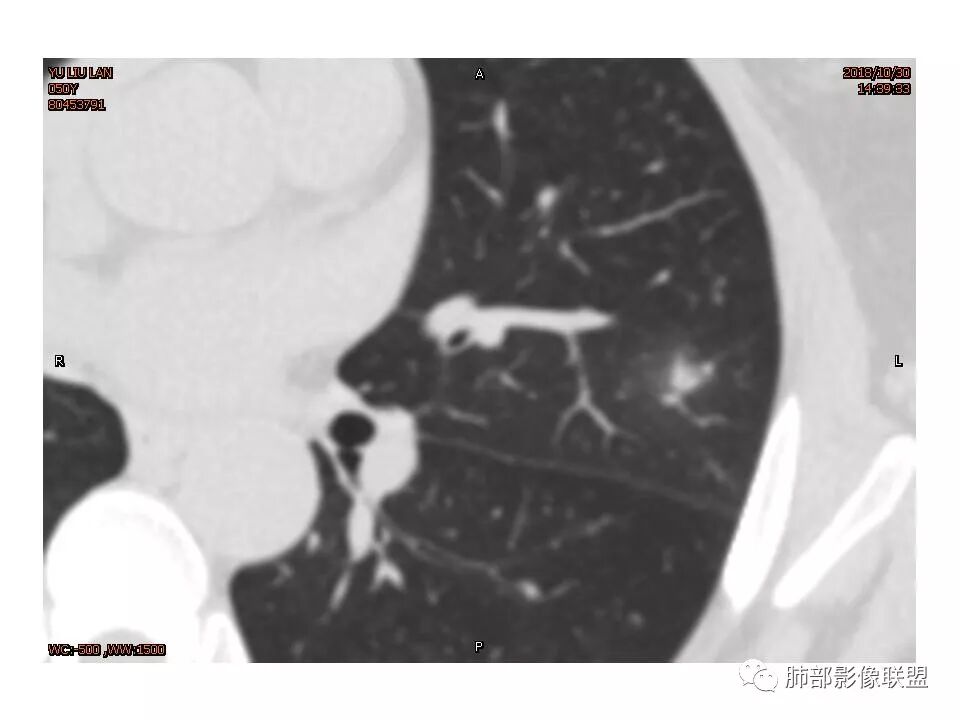

左肺上叶后段病灶,有毛刺,有胸膜牵拉,有血管滋养,好像还可以看见内部空泡,深分叶,边界比较清楚,考虑恶性肿瘤。

左肺上叶实性不规则结节,有深分叶,短毛刺,有切迹,有血管集束,有胸膜牵拉,常规考虑恶性,鉴别炎性结节

女性,左上肺实性结节,有毛刺,有血管进入,边缘彭隆,月牙铲,深分叶,边界比较清楚,胸膜牵拉,考虑腺癌。

结节样病灶,u型征,病灶内可见细支气管管,增强可见血管进入,略增粗,病灶周围有晕,有软毛刺,局部叶间胸膜有牵拉,考虑良性炎性病灶,抗炎后复查。

细小毛刺,梳状平行,周围边缘模糊晕,血管未收侵犯,支气管未见牵拉扩张,多条淋巴道与胸膜相联,倾向于炎性病变

1.胸膜下略不规则实性密度结节影,孤立,缺乏典型深分叶,可见淡薄边界模糊磨玻璃晕,可见相对细长软毛刺。

2.如南边老师分析,病灶缺乏边缘膨隆优势,甚至部分平直内收。

3.病灶收缩力不强,整体强化程度不显著。

4.综上,病灶更符合炎性,如隐球菌感染等,而不大符合肺腺癌。具体到机化性肺炎略有些出乎预料。